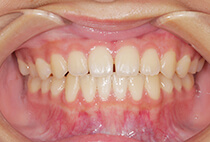

治療前

治療後

しっかり前歯を下げるために、インプラントアンカーを使用してコントロールしました。

かみ合わせが整うと咬筋の過緊張が改善。

過緊張による筋肉肥大も改善しフェイスラインもすっきりしました。